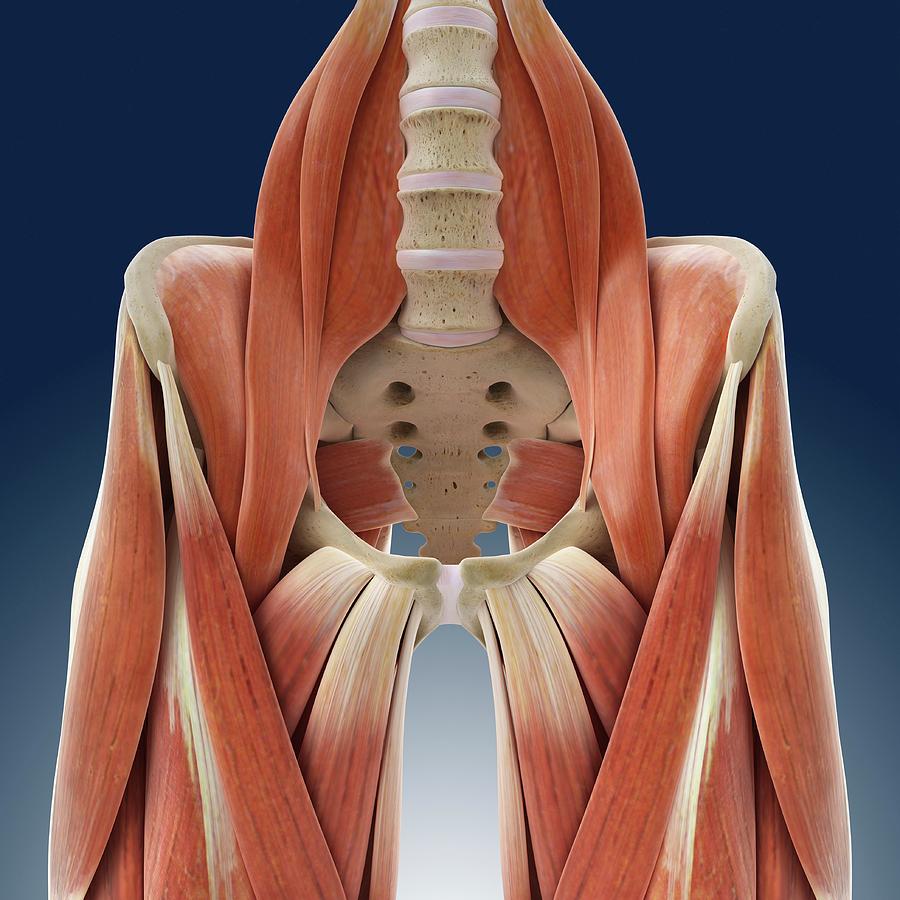

Mușchii